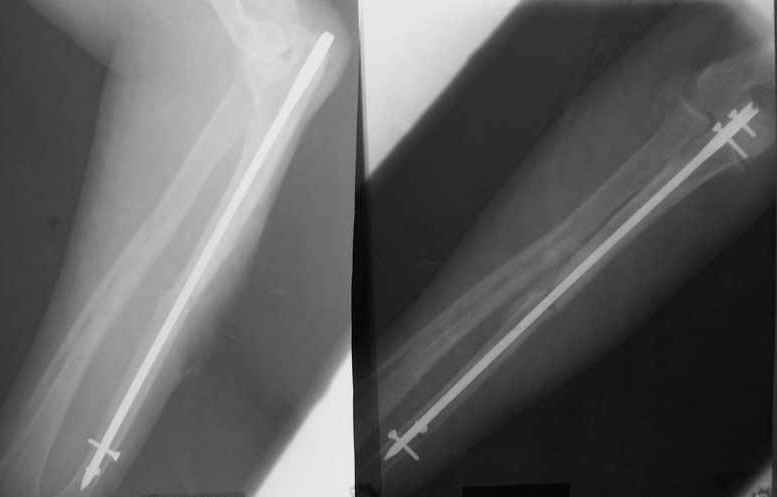

Интерлокинг костей предплечья

Уважаемые коллеги! Доводим до Вашего сведения наш скромный опыт применения блокирующего остеосинтеза локтевой кости (4случая), четверо пациентов с ложными суставами локтевой кости.

Во всех случаях оперировали открыто с костной аутопластикой. Технических проблем введения штифтов не было. В одном случае отвалилась резьбовая часть спицы при прокс. блоке (оставлена как блокирующий винт). Дистальное блокирование осуществляли используя вместо кондуктора сп. Киршнера изгибая ее конец о край кондуктора на необходимую длину до отверстий. Наши первые впечатления классные. Очень быстрая функциональная реабилитация без гипса и консолидация через 2 мц. На представленных фотографиях двое пациентов. Тот, у которого якобы не срастается лучевая кость на АО пластине, уже катался на горн. лыжах, а сейчас опять уехал на Эльбрус - экстремал ,,,нов.

С уважением Нагога Александр, ортопедическая клиника ОРТО, Самара.